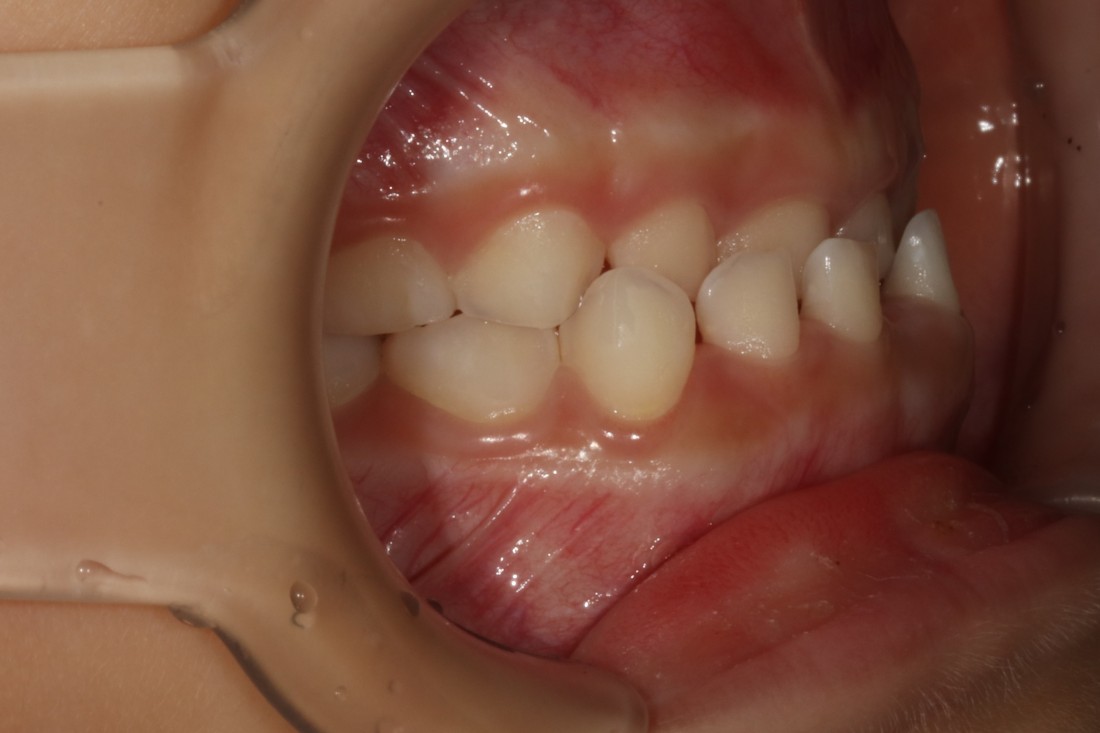

어린이부정교합의 케이스로

반대교합 / 과개교합 / 개방교합 정도로

크게 세 가지 유형으로 나누어서

각 케이스에 맞는 프리올소 교정장치 타입을

추천해드리고 있습니다.